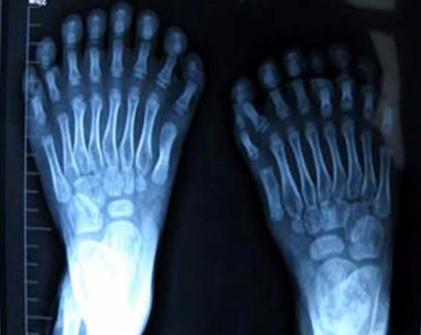

Šetogodišnji dječak iz provincije Shenyang na sjevero-istoku Kine do jučer je bio vlasnik tužnog svjetskog rekorda - na rukama je imao 15 prstiju, a na nogama 16.

Lokalni mediji javljaju da je dječak sinoć uspješno operiran te da su mu suvišni prsti amputirani u vrlo složenoj operaciji. Cilj zahvata bio je poboljšati dječakove sposobnosti hodanja i rukovanja stvarima.

Deformacija je genetski nasljedna i poznata pod nazivom polidaktilnost. Stručnjaci upozoravaju da poremećaj uzrokuje ekstremno zagađen zrak u Kini koji je prepun smoga i sitnih čestica prašine.